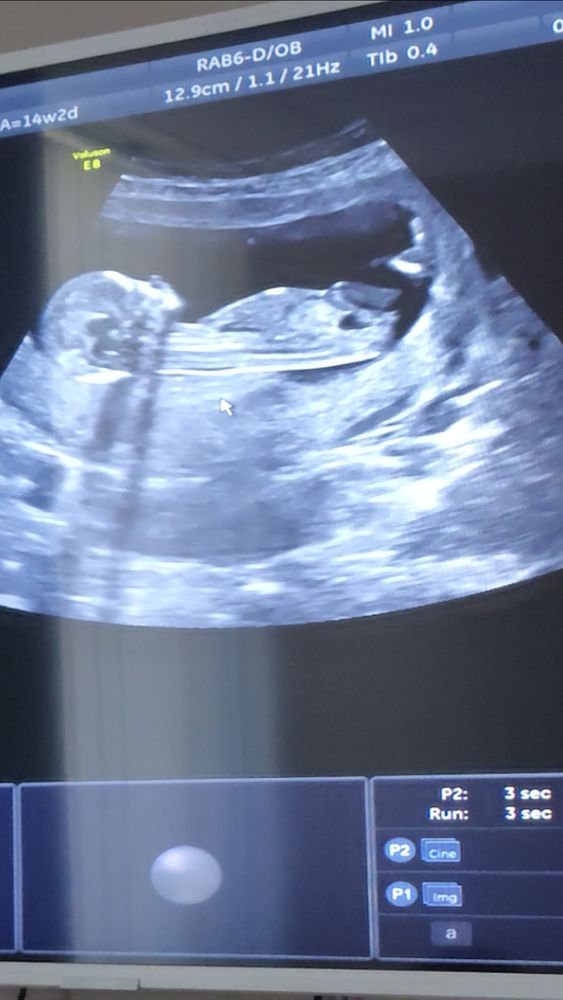

Мальчик или девочка? Фото узи

Здесь более вероятен женский пол. А торчит - половой бугорок. В данном случае - клитор))

А почему все за девочку? 😄на первой фотографии похожа, а на остальных же прям торчит что-то, что не очень на девочку похоже))